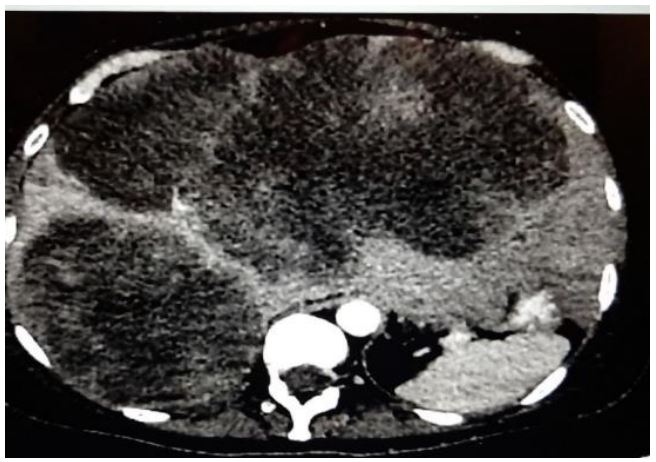

Initially, 4 cm right-sided breast mass was identified on ultrasound (Figure 1). From there, a core needle biopsy was performed, which demonstrated a fibroadenoma. However, the histology from the ensuing lumpectomy demonstrated the presence of a malignant PT. After several courses of radiotherapy, the discovery of the right-sided axillary lymph node necessitated PET-CT, which showed high intake of FDG (Figure 2). The corresponding core needle biopsy confirmed that it contained metastasized PT. After performing bilateral mastectomy with right axillary lymph node dissection, the histology proved that the breasts were clear, but that 1/16 lymph nodes contained PT. Significantly, the occurrence of an additional axillary mass a couple months later prompted an abdominal and chest CT. This demonstrated metastases in the axillary, mediastinal, and retroperitoneal lymph nodes, with liver metastasis (Figures 3 and 4). No further biopsies were performed, and follow-up abdominal and chest CT demonstrated that the metastases had increased in size (Figures 5 and 6).

Figure 2: PET-CT demonstrating high intake of FDG in the right axillary lymph node.